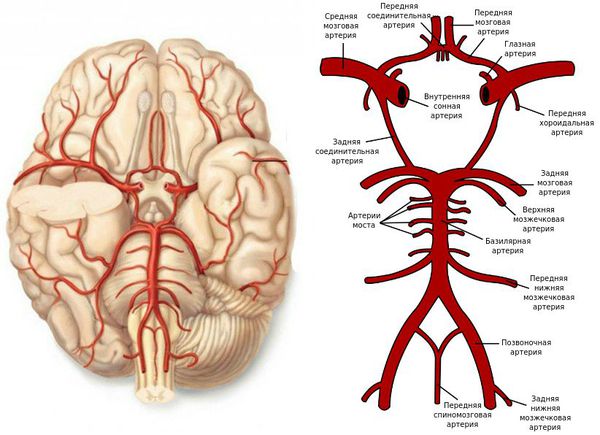

Анатомия: Задняя соединительная артерия мозга

:max_bytes(150000):strip_icc()/CircleofWillis-87378170-3ece0502a02949dd82310d723e0d4c98.jpg)

Раздел: Фотоэссе